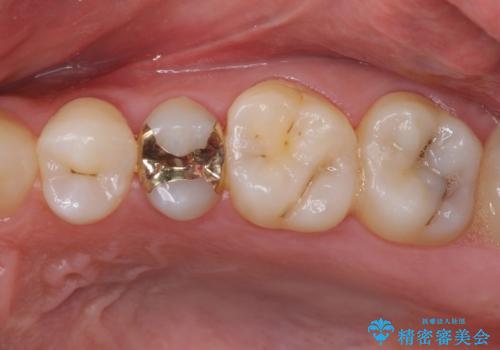

歯肉が痩せてしまっている状態を改善するため、口蓋から歯肉の結合組織を採取し、移植することで厚みを増大させることとし、その後オールセラミックブリッジにて補綴治療を行うこととしました。

1回の歯肉移植により歯肉の厚みは大幅に改善されましたが、折角なのでもう少し大きくしたいとの要望があり、2回目の処置も行うこととしました。

厚みも高さも十分な歯肉量を獲得することができました。